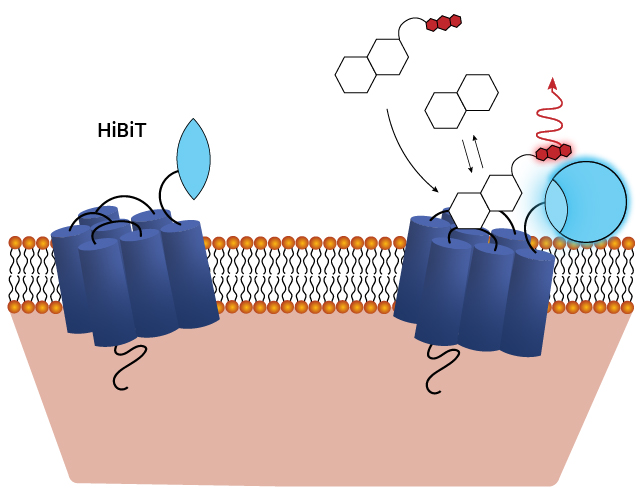

NanoBRET® target engagement is a highly sensitive and quantitative method for measuring ligand binding. This involves labeling the GPCR with a HiBiT tag (via transient transfection or CRISPR/Cas9) and labeling the ligand with a fluorophore. When the ligand binds to the GPCR, their close proximity generates energy transfer, resulting in a fluorescence signal that enables precise quantification.

Schematic of assays utilizing the HiBiT/LgBiT reporter for monitoring ligand engagement via BRET. See details in this publication: The luminescent HiBiT peptide enables selective quantitation of G protein-coupled receptor ligand engagement and internalization in living cells.

Saturation binding of a Clozapine NanoBRET® tracer to five GPCRs in the α-adrenergic receptor family. See details in this publication: An integrated approach toward NanoBRET tracers for analysis of GPCR ligand engagement.